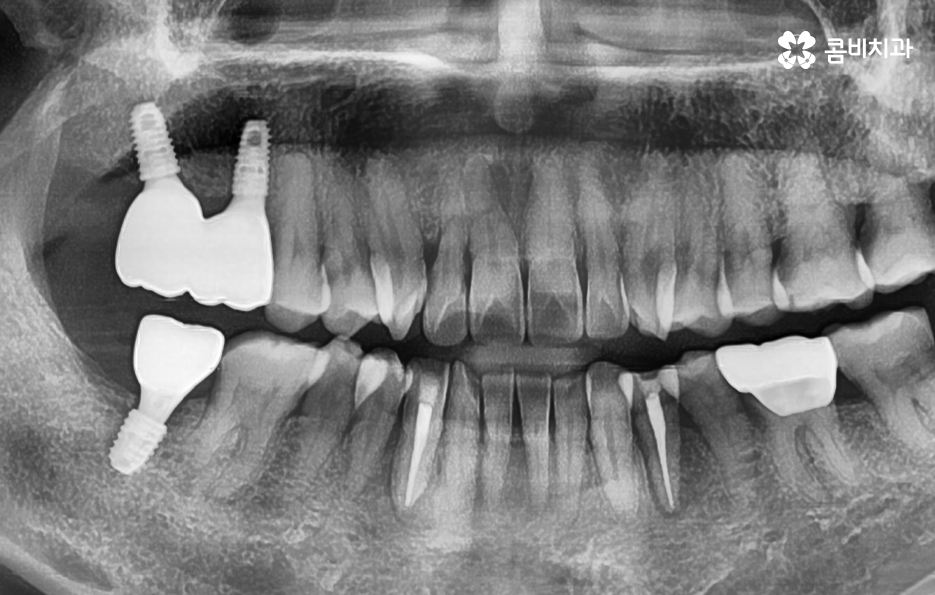

그래서 오늘은 많은 분들이 어금니 상실로 인해 어금니 임플란트를 알아보시기 때문에 어금니 임플란트 기간에 대해 알아보면서 치료 과정도 함께 알아보겠고 임플란트 종류 차이가 발생하는 이유에 대해서도 알아볼 거예요

일반적인 임플란트의 치료 과정은 충치나 치주염 등으로 치아를 발치하게 되었을 때 치아 발치 후 잇몸이 아물고 회복되기를 기다리고 있는데요. 잇몸이 충분히 회복된 후에 임플란트를 잇몸 뼈에 식립하는 것을 시작으로 치과 내원과 어금니 임플란트 기간에 대해 대략적으로 알아보면 내원 횟수는 약 45회 정도로 예상되며 평균적으로 34개월 정도면 치료가 마무리 되고 있어요

특히 노인분들의 경우에는 치아를 잃게 되는 주된 원인이 치주염이 심해져서 치아가 흔들리고 발치하게 되는 경우가 많으며 당뇨나 고혈압과 같은 전신질환이 있는 경우도 고려해야 하기 때문에 임플란트의 기본적인 치료 원리는 비슷하지만 각 개인에 따라서 치료기간과 치료 방법이 다소 차이가 날 수 있어요